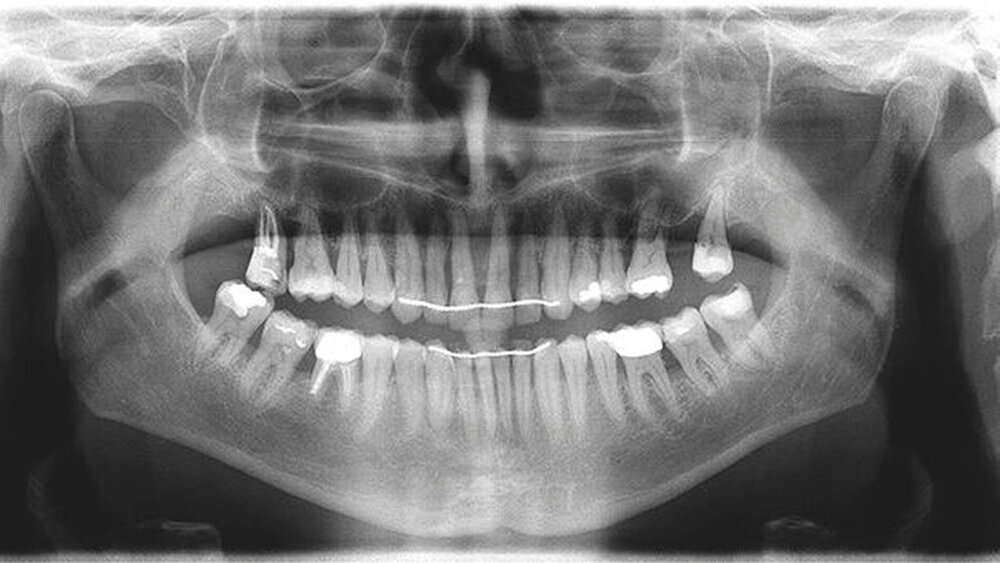

Röntgenologisch stellte sich im Orthopantomogramm der bereits intraoral ersichtliche horizontale und vertikale Knochenabbau mit Attachmentverlust an einzelnen Zähnen dar. Die Erhaltungswürdigkeit einzelner Zähne war aufgrund des starken Knochenverlustes beziehungsweise der Beeinträchtigung des Halteapparates als kritisch zu beurteilen.

Zudem wurde die Diagnose einer Parodontitis gestellt, die eine Rücküberweisung an den Hauszahnarzt erforderlich machte (Abbildung 2).

Die reine Intrusion von Zahn 11 konnte mit 2,5 mm beziffert werden, während Overjet und Overbite jeweils 2 mm und 3 mm betrugen (Abbildung 5). Die Abbildungen 6 bis 9 zeigen die Ergebnisse der Behandlung im zeitlichen Verlauf sowohl klinisch (Abbildungen 6 und 8) als auch in der bildgebenden Kontrolle (Abbildungen 7 und 9).